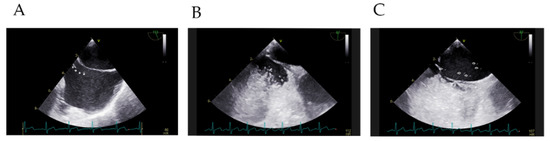

Objective Quantification of Bilateral Bubble Contrast Echocardiography Correlates with Systemic Oxygenation in Patients with Single Ventricle Circulation

by Ashley Phimister, Chana Bushee, Monica Merbach, Sai Alekha Challa, Amy Y. Pan and Andrew D. Spearman

J. Cardiovasc. Dev. Dis. 2024, 11(3), 84; https://doi.org/10.3390/jcdd11030084 - 1 Mar 2024

Bubble contrast echocardiography is commonly used to diagnose pulmonary arteriovenous malformations (PAVMs) in single ventricle congenital heart disease (CHD), yet previous studies inconsistently report a correlation between bubble echoes and oxygenation. In this study, we sought to re-evaluate the correlation between bubble echoes [...] Read more.

Bubble contrast echocardiography is commonly used to diagnose pulmonary arteriovenous malformations (PAVMs) in single ventricle congenital heart disease (CHD), yet previous studies inconsistently report a correlation between bubble echoes and oxygenation. In this study, we sought to re-evaluate the correlation between bubble echoes and oxygenation by assessing total bilateral shunting and unilateral shunting. We conducted a single-center, retrospective study of patients with single ventricle CHD and previous Glenn palliation who underwent a cardiac catheterization and bubble echocardiogram during the same procedure from 2011 to 2020. Spearman’s rank correlation was performed to examine the relationship between total bilateral shunting and measures of systemic oxygenation, as well as unilateral shunting and ipsilateral pulmonary vein oxygenation. For all patients (n = 72), total bilateral shunting moderately correlated with peripheral oxygen saturation (SpO2) (rs = −0.44, p < 0.0001). For patients with Glenn/Kawashima circulation (n = 49), total bilateral shunting was moderately correlated (SpO2: rs = −0.38, p < 0.01). In contrast, unilateral shunting did not correlate with ipsilateral pulmonary vein oxygenation for any vein measured (p = 0.16–p > 0.99). In conclusion, the total burden of bilateral bubble shunting correlated with systemic oxygenation and may better reflect the total PAVM burden from all lung segments. Unilateral correlation may be adversely influenced by non-standardized approaches to pulmonary vein sampling. Full article